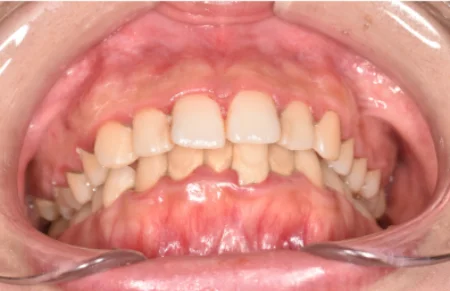

一般歯科 2023.0430代女性「歯のメインテナンスをしたい」目立つ着色を、専門的な歯のクリーニング「PMTC」とパウダーを用いた「エアフロー」できれいに落とし、本来の歯の色を取り戻した症例